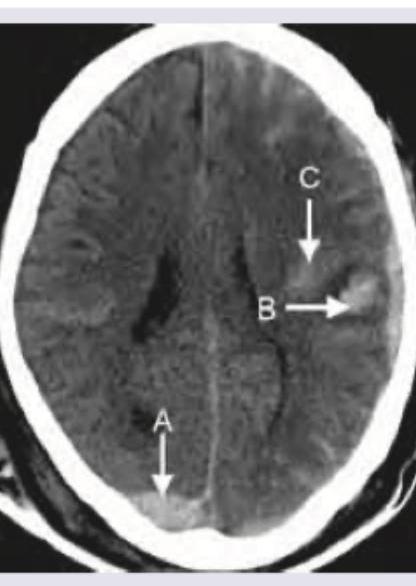

Which is correct about the intracranial bleeding shown below?

Explanation: ***Chronic subdural hematoma, hypodensity*** - The image displays a crescent-shaped collection of fluid with **hypodense characteristics** (darker than brain parenchyma) that crosses suture lines, which is typical for a subdural hematoma. - The **hypodensity indicates older, chronic blood** where the hemoglobin has degraded, differentiating it from acute (hyperdense) or subacute (isodense) collections. *Acute subdural hematoma, hypodensity* - An **acute subdural hematoma** would typically appear **hyperdense** (bright) on CT due to fresh blood. - The observed collection is clearly hypodense, ruling out an acute presentation. *Chronic epidural hematoma, hyperdensity* - An **epidural hematoma** is typically **lenticular (lens-shaped)** and does not cross suture lines, unlike the crescent shape seen here. - While chronic blood *can* be hypodense, an epidural hematoma by definition is outside the dura mater and would not present with this morphology. *Acute epidural hematoma, hyperdensity* - An **acute epidural hematoma** is characterized by a **lenticular (lens-shaped) hyperdense** collection of blood, which is distinctly different from the crescent-shaped, hypodense collection in the image. - Epidural hematomas occur between the dura mater and the skull, typically from arterial injury, and are bound by sutures.

Explanation: ***A = Extradural hemorrhage, B = Subdural hemorrhage, C = Contusion*** - Image **A** shows a **biconvex (lenticular)** shape, typically indicating an **extradural (epidural) hemorrhage** due to arterial bleeding, often from the middle meningeal artery. This collection is limited by the cranial sutures. - Image **B** (pointed to directly by the arrow) shows a **crescent-shaped** collection of blood that extends along the surface of the brain, consistent with a **subdural hemorrhage**, usually caused by venous bleeding from bridging veins. - Image **C** points to an area within the brain parenchyma that appears heterogeneous with scattered hyperdensities and hypodensities, characteristic of a **contusion** (bruising of the brain tissue). *A = Subdural hemorrhage, B = Extradural hemorrhage, C = Contusion* - This option incorrectly identifies the characteristic shapes of extradural and subdural hemorrhages. **Extradural hemorrhages** are typically biconvex (*lenticular*), while **subdural hemorrhages** are crescent-shaped, directly opposite to what is suggested for A and B here. - The imaging features for A and B in the provided image unequivocally differentiate them, making this option incorrect. *A = Contusion, B = Subdural hemorrhage, C = Extradural hemorrhage* - This option misidentifies all three lesions. The lesion at **A** is clearly an extradural hematoma due to its shape and location, not a contusion. - The lesion at **C** is intraparenchymal and heterogeneous, consistent with a contusion, not an extradural hemorrhage which would be located outside the brain parenchyma. *A = Extradural hemorrhage, B = Subdural hemorrhage, C = Subarachnoid hemorrhage* - While A and B are correctly identified as extradural and subdural hemorrhages, respectively, the lesion at **C** is incorrectly identified as a subarachnoid hemorrhage. - A **subarachnoid hemorrhage** would appear as hyperdensity within the sulci and basal cisterns, which is not what is shown by arrow C; C points to an intraparenchymal lesion typical of a contusion.